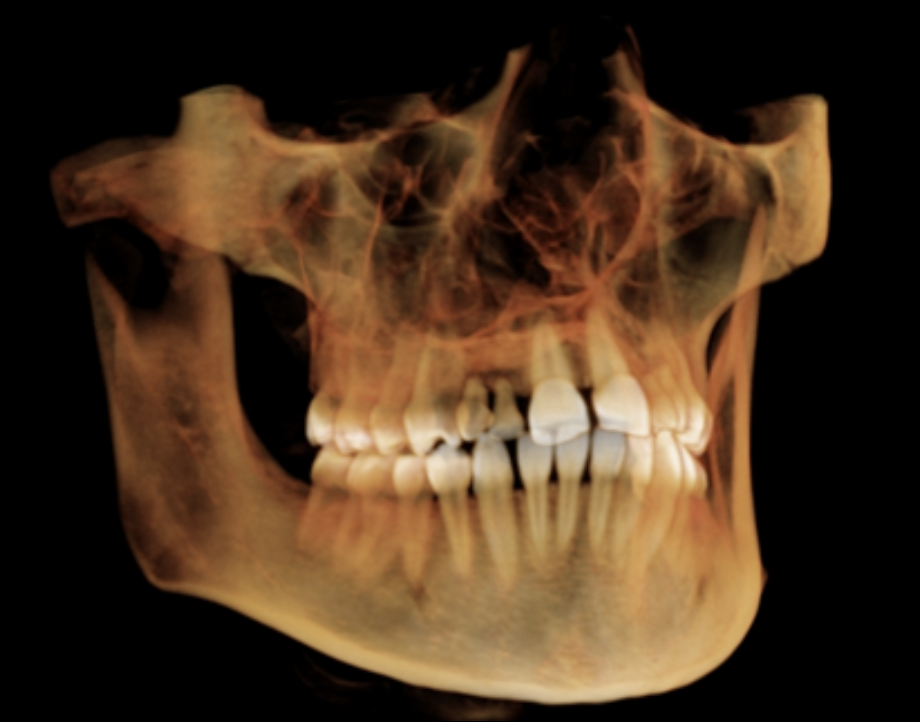

What view?

Sagittal